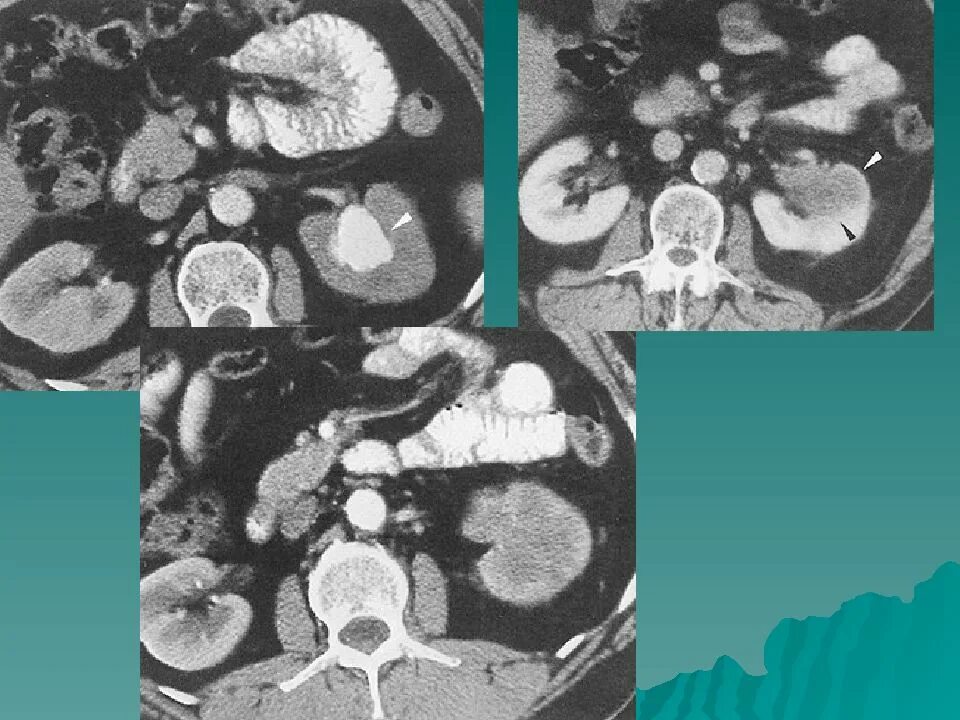

Заболевание кт